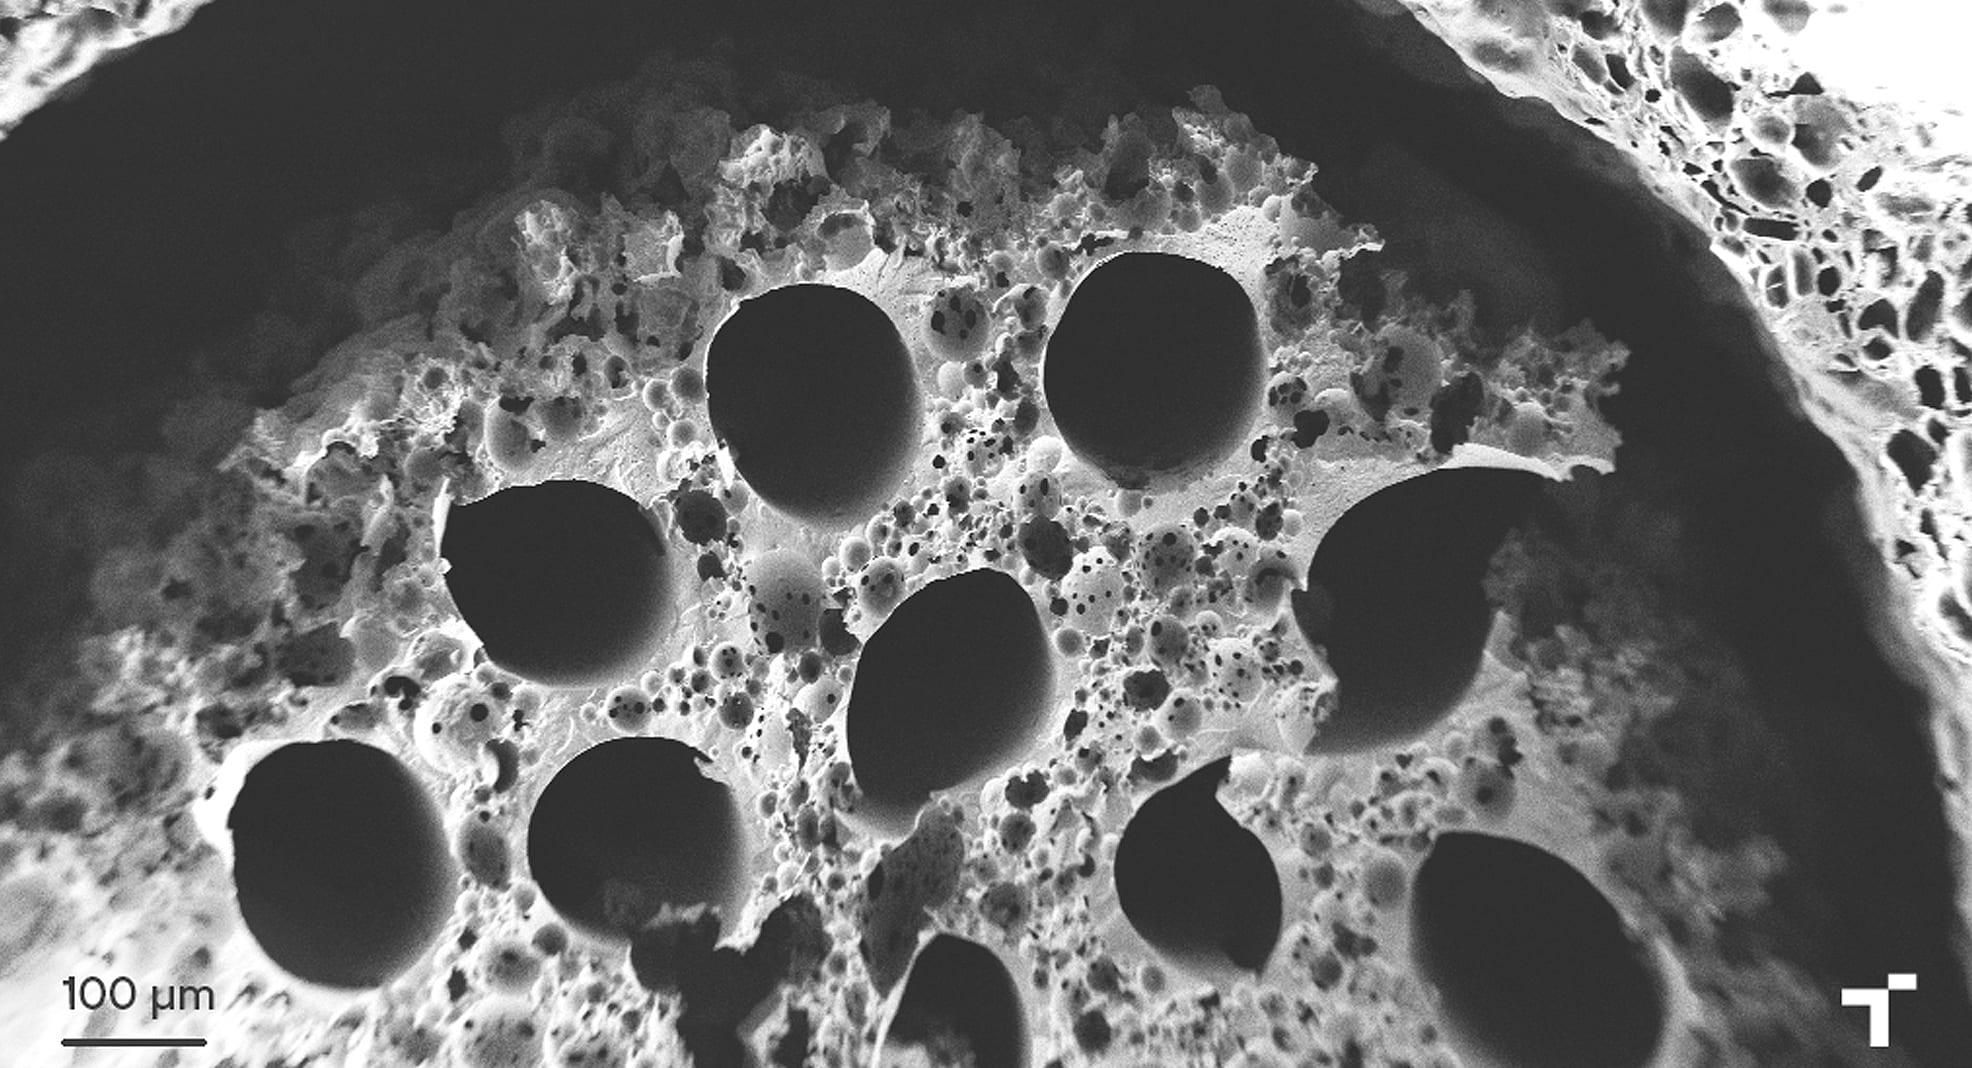

Zentro teknologikoak, proiektua koordinatzeaz gainera, zentroaren espezializazio-arloetan (gainazalen ingeniaritzan eta fabrikazio aurreratuan) integratutako teknologiak garatu ditu; hala nola, eskala mikrometrikoan garatu du polimeroen prozesaketa, inplantearen egitura tubularra (mikrokanalez osaturikoa) optimizatzeko xedez, jatorrizko nerbioaren geometria mimetizatuz.